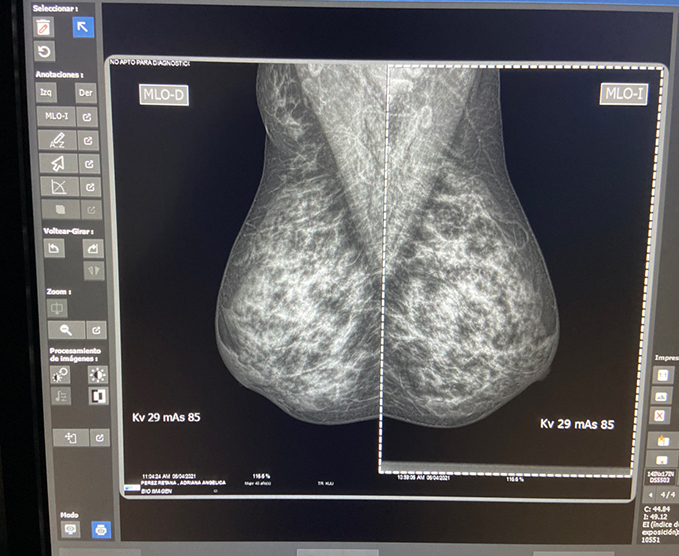

Es una exploración específica para el seno, que se realiza a través de rayos X. En mujeres mayores de 40 años se utiliza generalmente para buscar signos precoces de cáncer de seno. Los expertos coinciden en que el éxito del tratamiento de esta enfermedad va unido al diagnostico temprano, en lo cual la mamografía tiene una importancia determinante.

Cada seno se coloca en un soporte perpendicular al tubo de rayos X del Mamógrafo y se realiza una comprensión sobre el mismo; esta comprensión pudiera generar alguna molestia, pero es indispensable para obtener una imagen nítida de los tejidos. El haz de rayos X atraviesa el seno y la imagen de este se imprime en una película radiográfica, o es enviada a un monitor para ser estudiada por el médico radiólogo.